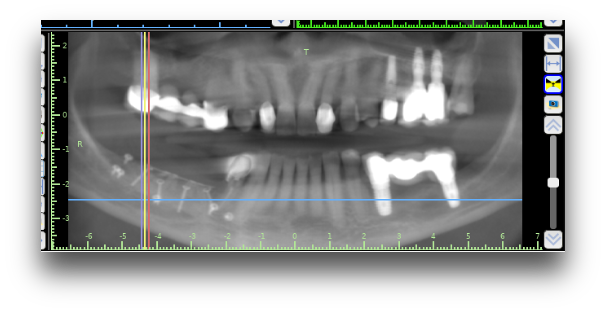

After 5 months of bone augmentation and healing, new bone formation was assessed clinically, radiographically and by histology of bone biopsies. All measurements were done by one specialist in oral radiology at UiB in Bergen.

After surgery, there were statistically significant differences between groups in terms of post-surgery total length of reconstructed areas with 22 mm and 18 mm for test and control group respectively (p=0.019 Mann-Whitney test). Both test and control regenerative surgical interventions have provided a significant increase in bone width over time at the level of the defect (p<0.05). The histology of biopsies demonstrated vertical newly formed bone in all the augmented areas. 21 out of the 60 included patients have undergone the final visits of implant placement, 5 months after bone augmentation procedure (10 in the control group and 11 in the test group). All patients had sufficient bone for dental implant installation. Some of these patients have successfully received prosthetic dentures restoring function and aesthetic prosthetic rehabilitation.

CBCT scan after MAXIBONE augmentation procedure